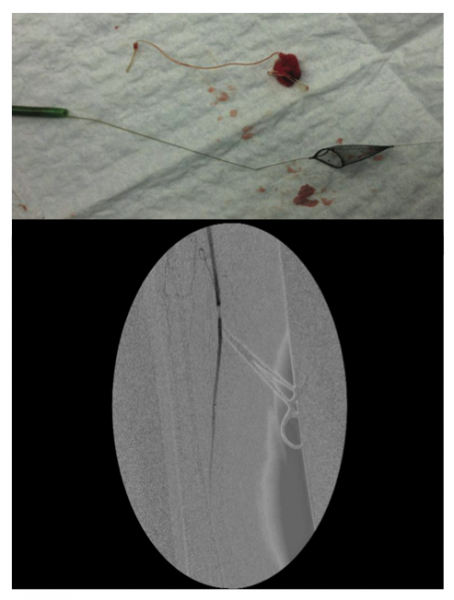

Abstract 10: Endovascular Management of Vascular Closure Device Complications

Kuldeep Singh, MD; Sumeet Singh Goraya; Khanjan Nagarsheth, MD; Simrat Suri, MD

Introduction: Vascular closure devices (VCD) can lead to devastating consequences if deployed incorrectly. Objective: We undertook this study to examine endovascular management of complications caused by closure devices. We also present a novel technique to remove a misdeployed closure device. Methods: A PubMed, Ovid, and Google Scholar literature search was formed as it pertains to this topic. We also present a novel technique to remove a misdeployed closure device. Results: A 76-year-old female was noted to have an embolized Angio-Seal device (St. Jude Medical) after catheterization. From the contralateral femoral artery, an 8 Fr destination sheath was placed proximal to the embolus. A SpiderFX protection filter (Covidien) was deployed past the embolus. The sheath and the filter containing the embolized Angio-Seal device were removed. A final angiogram revealed complete arterial patency. We identified 14 studies and 455 patients who had VCD complications managed by endovascular means. Mean age was 62.7 years, 52.8% were male. Arterial access involved puncture of the superficial femoral artery in 52.9% of cases, the common femoral in 33.3% of cases, and profunda or external iliac artery in 13.9% of cases. Sheath size ranged from 4 Fr to 10 Fr. There was no association between sheath size and frequency of complications. The method of VCD retrieval included catheter thrombolysis, snare, and flexible alligator forceps. Conclusion: The use of VCD is becoming more commonplace in endovascular procedures. Limb-threatening ischemia can occur if deployed incorrectly. Novel endovascular techniques can be employed to retrieve these devices and restore arterial flow to the limb.